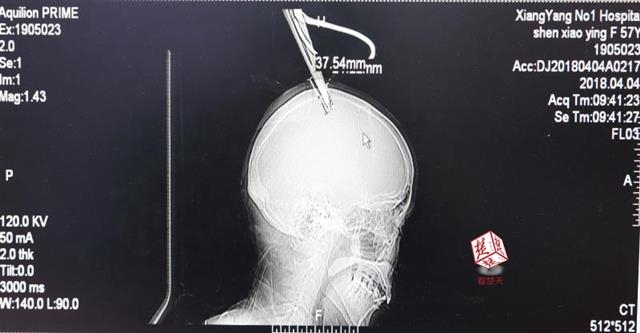

女子顱骨插進剪刀 不慌不忙坐公交車就醫(yī)

醫(yī)生檢查發(fā)現(xiàn),剪刀刀尖斜嵌在沈某顱骨里,離腦髓只有兩三毫米。所幸是斜著插進去,如果是垂直刺入,很有可能造成癱瘓。

4月4日清晨,襄陽市樊城區(qū)太平店鎮(zhèn)57歲的農(nóng)村婦女沈某,在采摘香椿嫩芽時,綁在竹桿上的剪刀因竹子腐朽不慎折斷,剪刀斜插入頭顱。經(jīng)過及時搶救,目前脫離生命危險。

“當時感覺還好,就是頭有點木?!鄙蚰痴f,由于自己感覺沒什么大礙,便沒坐120急救車,而是和家人一起坐了一個小時的公交車趕到市區(qū)醫(yī)院。

醫(yī)生檢查發(fā)現(xiàn),剪刀刀尖斜嵌在沈某顱骨里,離腦髓只有兩三毫米。所幸是斜著插進去,如果是垂直刺入,很有可能造成癱瘓。最終經(jīng)過手術(shù),剪刀被取出,沈某目前仍在ICU進一步觀察。